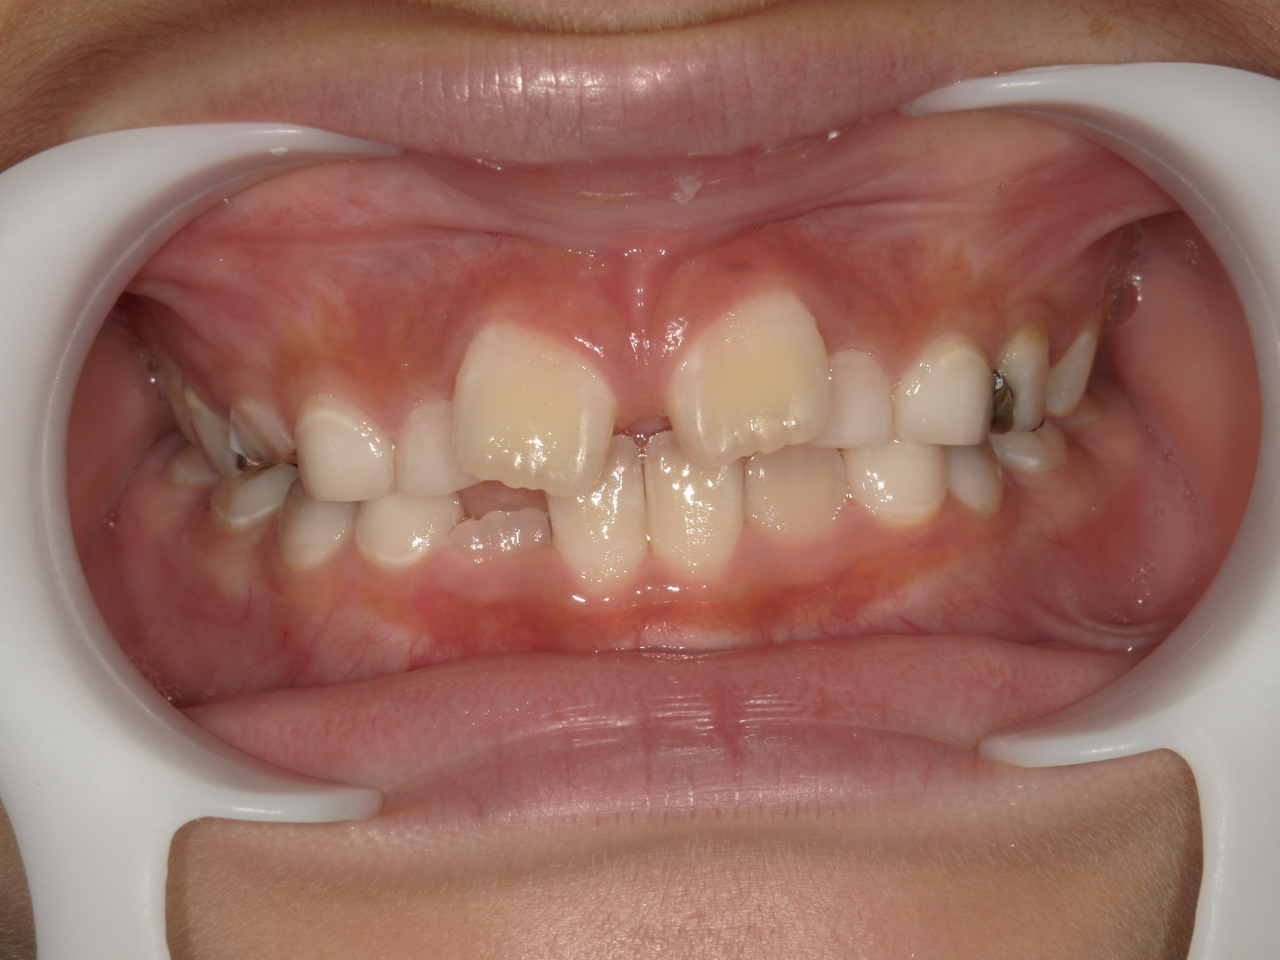

治療前

治療説明

歯科矯正で取り外し可能な矯正方法である床矯正とチンキャップで治療しました

治療期間 4年6か月

治療費用300000 円

治療後

治療の副作用(リスク)歯の動き方には個人差があり、予想された治療期間が延長する可能性があります。。床矯正の使用状況、矯正歯科治療には患者さんの協力が必要であり、それらが治療結果や治療期間に影響します。2次矯正が必要になる場合もあります。